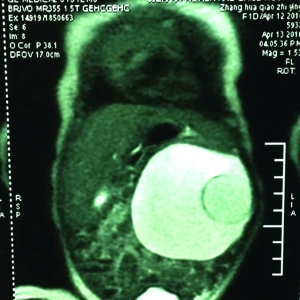

B超畫面

王壽青說,臨床調(diào)查顯示,寄生胎的發(fā)病幾率約為百萬分之一。從苗苗入院時的B超,可以清楚地看到她腹中10厘米左右的囊性包塊,可以看到胚胎的頭、腿、脊柱。“因為胚胎已經(jīng)部分壞死,留在肚子里可能會讓主體感染。同時,由于胚胎與主體血管相通,會分散主體吸收的營養(yǎng),隨著主體長大,形成惡性腫瘤。”王壽青說,基于此,4月19日,他們給苗苗做了手術(shù)。手術(shù)時,醫(yī)生們先將囊性包塊中近200ml的水取出,之后又將胚胎順利取出。